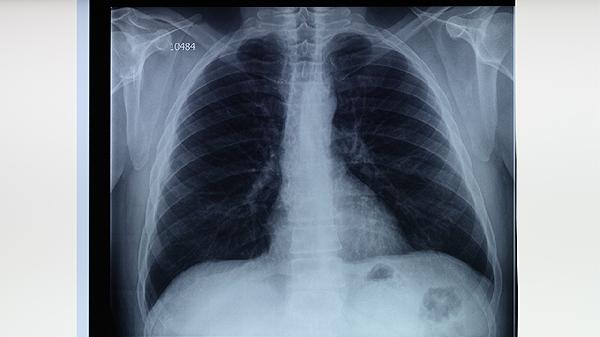

肺结核患者需严格遵医嘱完成6-9个月的规范治疗,不可自行停药或调整剂量。治疗期间应保持高蛋白高维生素饮食,适当进行有氧运动增强体质。注意隔离防护避免传染他人,定期复查胸部影像学和痰菌检查。出现药物不良反应应及时就医,耐药结核患者需根据药敏试验结果调整方案。保持居室通风和良好作息习惯有助于康复。